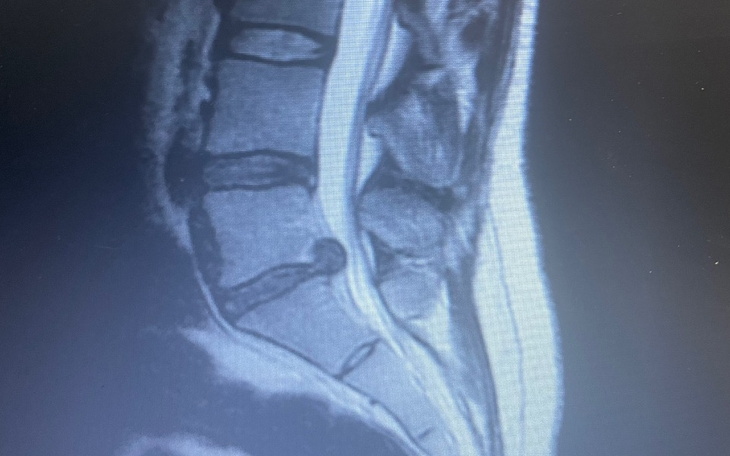

Cześć :) Nazywam się Ada, mam 24 lata. Od 1,5 roku moje życie to koszmar. Z dnia na dzień przestałam chodzić, odczuwałam straszne promieniowania w różne części ciała. Musieli mnie myć, sadzać na toalecie i pomagać we wszystkim. Po kilku miesiącach zrobili mi rezonans i wyszło, ze mam wypuklinę, dysk wypadł, zwyrodniania i mocny ucisk na nerwy. Po kolejnych kilku miesiącach przeszłam operacje, po której miało być super.. owszem chodzę, ale nie jak zdrowy człowiek. Nadal mam promieniowania i wystarczy jeden zły ruch bym znów była przywiązana do łóżka.